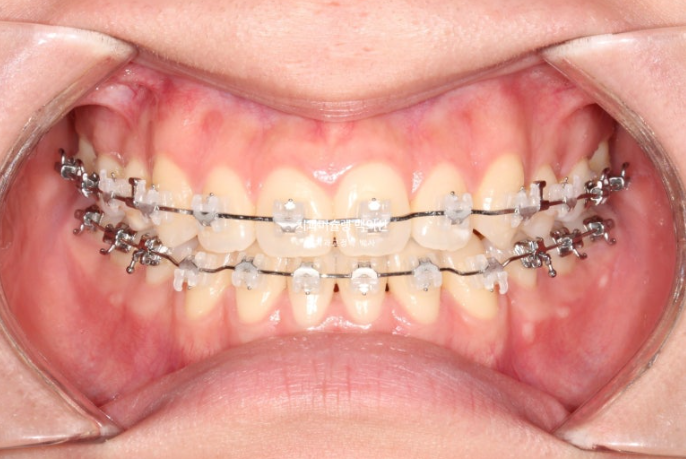

25.10

중심선은 정확히 맞습니다.

물샐틈 없는 1급 교합입니다.

총 치료기간은 2년에서 한달 모자란 1년 11개월 입니다.

어긋나 있던 위아래 중심선이 일치되었습니다.

앞니가 거꾸로 물리는 반대교합이 해결되었습니다.